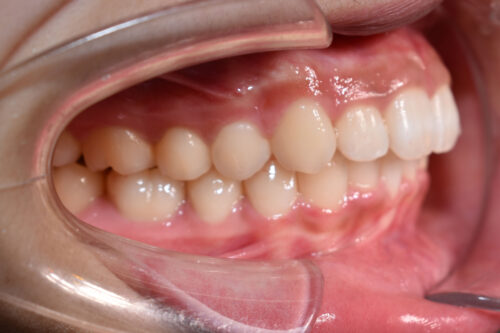

ワイヤー矯正治療7か月後です。

本症例も

矯正治療の精密検査後

非抜歯矯正治療計画を立案しました。